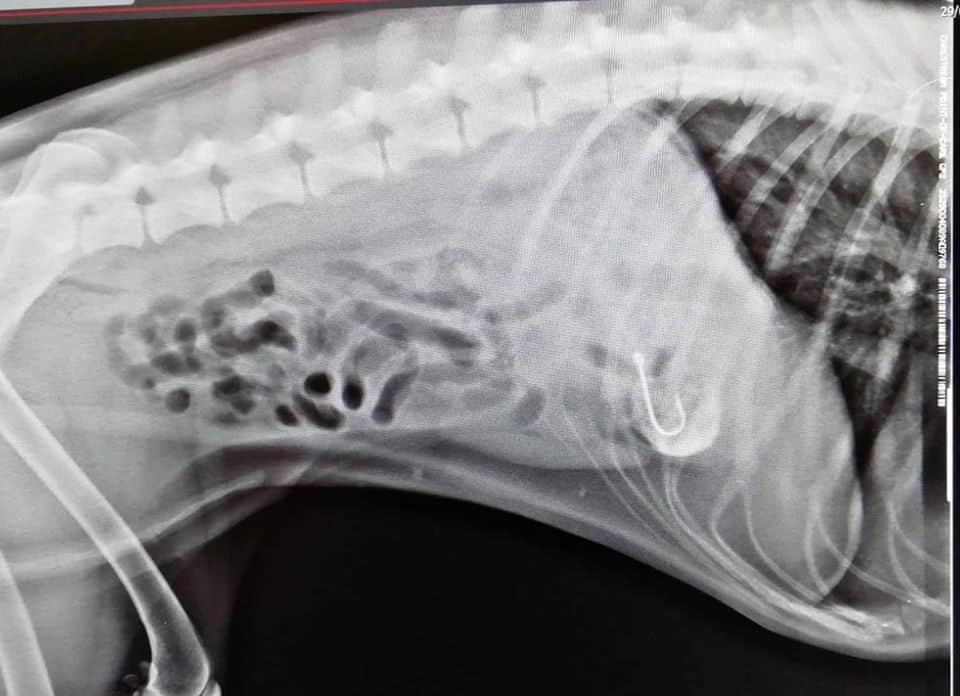

Appello lanciato anche dai Veterinari Associati che sui social hanno pubblicato le foto dell’amo ingerito da una cagnolina.

In questo caso a passarci i guai è stata una bella cagnolina che aveva ingerito il gustoso bocconcino di cannolicchio fresco che nascondeva però un pericoloso amo da 4cm, l’abbiamo dovuta operare e si è salvata!”